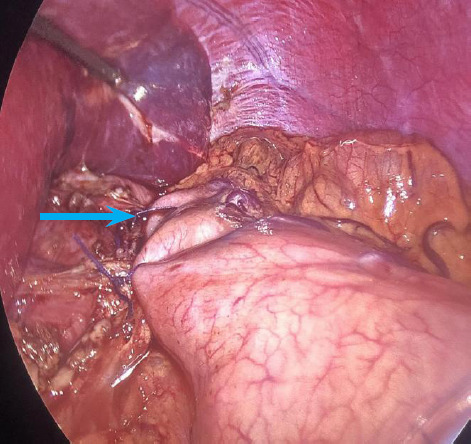

摘要:贲门失弛缓症是一种影响下食道括约肌和食道体的罕见疾病。由于其症状广泛,因此很难诊断。在此,我们报告了 9 个月内的三例贲门失弛缓症病例。第一例患者是一名 18 岁的男性,出现吞咽困难,经过吞钡和高分辨率测压(HRM)检查发现患有贲门失弛缓症。第二例患者是一名 37 岁的女性,由于患有多种并发症,诊断过程漫长,最终在吞钡检查中发现了贲门失弛缓症。第三例患者是一名 47 岁的女性,在吞钡检查中被迅速确诊。所有病例均通过腹腔镜海勒氏肌切开术和前路多氏胃底折叠术获得成功治疗。本系列病例强调了延误诊断的可能性,以及早期识别、有针对性的诊断方法和手术治疗效果的重要性。

Abstract: Achalasia cardia is a rare disorder that impacts the lower esophageal sphincter and esophageal body. Due to its wide range of symptoms, it can be difficult to diagnose. Here we report three cases of Achalasia Cardia during a period of 9 months. The first patient, an 18-year-old male, presented with dysphagia and was evaluated with barium swallow and high-resolution manometry (HRM) revealing Achalasia Cardia. In the second case, a 37-year-old female had a prolonged diagnostic journey due to multiple comorbidities before a barium swallow finally revealed achalasia cardia. The third patient, a 47-year-old female was promptly diagnosed with barium swallow. All the cases were successfully treated with laparoscopic Heller's myotomy with anterior Dor's fundoplication. This case series highlights the potential for delayed diagnosis and the importance of early recognition, tailored diagnostic approaches, and the efficacy of surgical management.